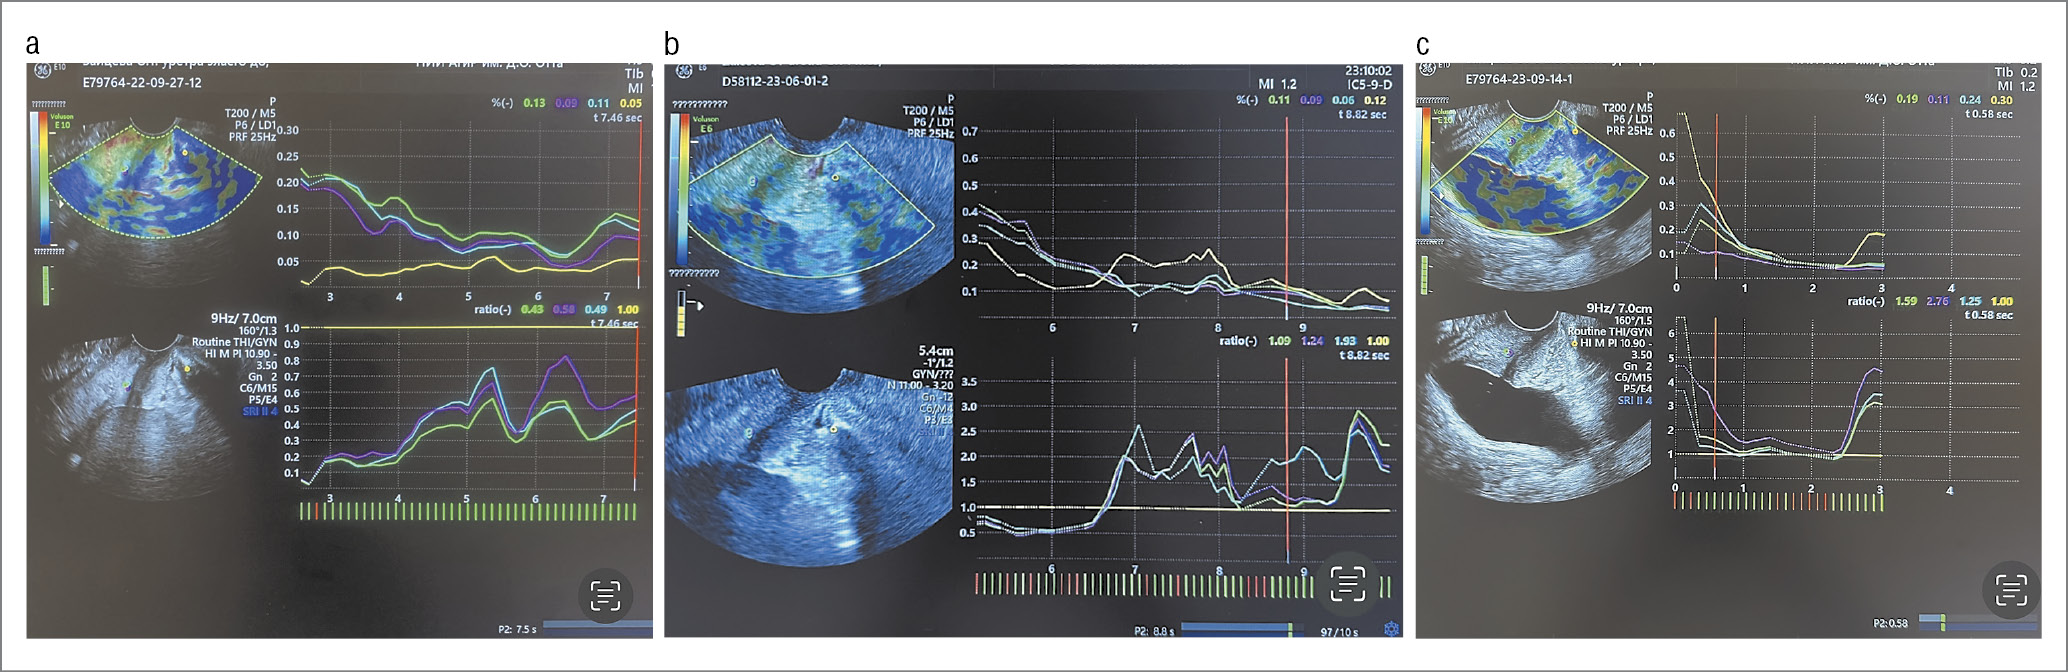

Клинический случай. Пациентке Е. 55 лет с СНМ легкой степени тяжести выполнили парауретральное введение препарата EsteFILL® intim. После процедуры через 1 и 6 мес отсутствовали эпизоды СНМ по данным дневников мочеиспускания, сохранялся отрицательный кашлевой тест. По данным УЗИ в течение всего периода наблюдения препарат визуализировали в парауретральной области, наблюдали уменьшение мобильности уретры. Ротация угла α уретры до процедуры составила 30,1, через 1 и 6 мес – 12,5 и 19° соответственно. У обследуемой после процедуры выявлено повышение жесткости тканей парауретральной области задней стенки ПО уретры. При этом значение SR тканей до лечения составило 0,50 у.е., через 1 и 6 мес после процедуры – 1,42 и 1,86 у.е. (рис. 7). Пациентка отмечала улучшение КЖ по данным опросника и ВАШ.

Рис. 7. КЭ УВС трансперинеальным доступом у пациентки Е. 55 лет с СНМ до лечения (а), через 1 (b) и 6 (c) мес после парауретрального введения препарата EsteFILL® intim (ультразвуковые приборы Voluson E6 и Е10; мультичастотный трансвагинальный датчик RIC 5-9-D).

Fig. 7. Compression elastography of the urethrovesical junction using transperineal access in patient Е., 55 years old with stress urinary incontinence before treatment (a), 1 (b) and 6 (c) months after paraurethral injection of EsteFILL® intim drug (Voluson E6 and E10 ultrasound systems; RIC 5-9-D multifrequency transvaginal probe).